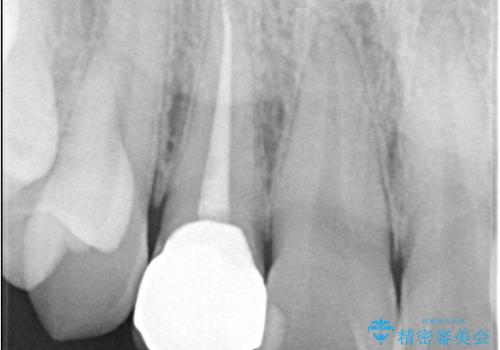

- 主訴:右上の前歯が何しなくても痛い

右上2番の歯に自発痛を認め、症状や歯髄診・レントゲン像から不可逆性歯髄炎と診断し、精密根管治療から歯冠補綴まで行うこととなりました。

初診時に歯髄診断を行い、不可逆性歯髄炎と診断し抜髄から補綴修復までの流れを説明し、精密根管治療、ファイバ-コア築造、オールセラミッククラウン(St)修復を行うこととしました。